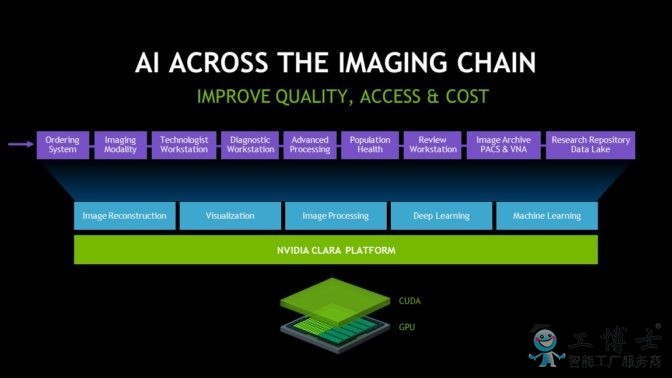

凭借最新发布的(de) Clara SDK,开发者可(kě)轻松利(lì)用他们拥有(yǒu)的任(rèn)何 GPU 平台部署 AI、可视化或计算密集型(xíng)应用(yòng)程(chéng)序(如影像(xiàng)重建(jiàn))。

十多年以(yǐ)来,NVIDIA GPU 一直在医(yī)学成像领域发挥关(guān)键作用。诊断影像(xiàng)形态依靠我们的(de) GPU 实现(xiàn)实时(shí)、顶尖的(de)影像重建,其(qí)中包(bāo)括用于减少 CT 扫描辐射剂量的迭代重建(jiàn)、可缩短核磁共振成像 (MRI) 扫描(miáo)时(shí)间的压(yā)缩感知以及能(néng)够提高(gāo)超声(shēng)影(yǐng)像质量的软件波束赋形。

Clara SDK 是开放(fàng)式 NVIDIA Clara 平台的组(zǔ)成部分,该(gāi)平台可助力医学成像行业打造并(bìng)部署(shǔ)先进的(de)成像(xiàng)应用程(chéng)序和支持 AI 的工作流程。

智能仪器(qì)和自动化工作流(liú)程已成(chéng)为现实。NVIDIA 正(zhèng)在与行(háng)业思想领(lǐng)袖开展(zhǎn)合作,让放射(shè)学(xué)能通过 NVIDIA Clara 平台跨越 AI 鸿沟。